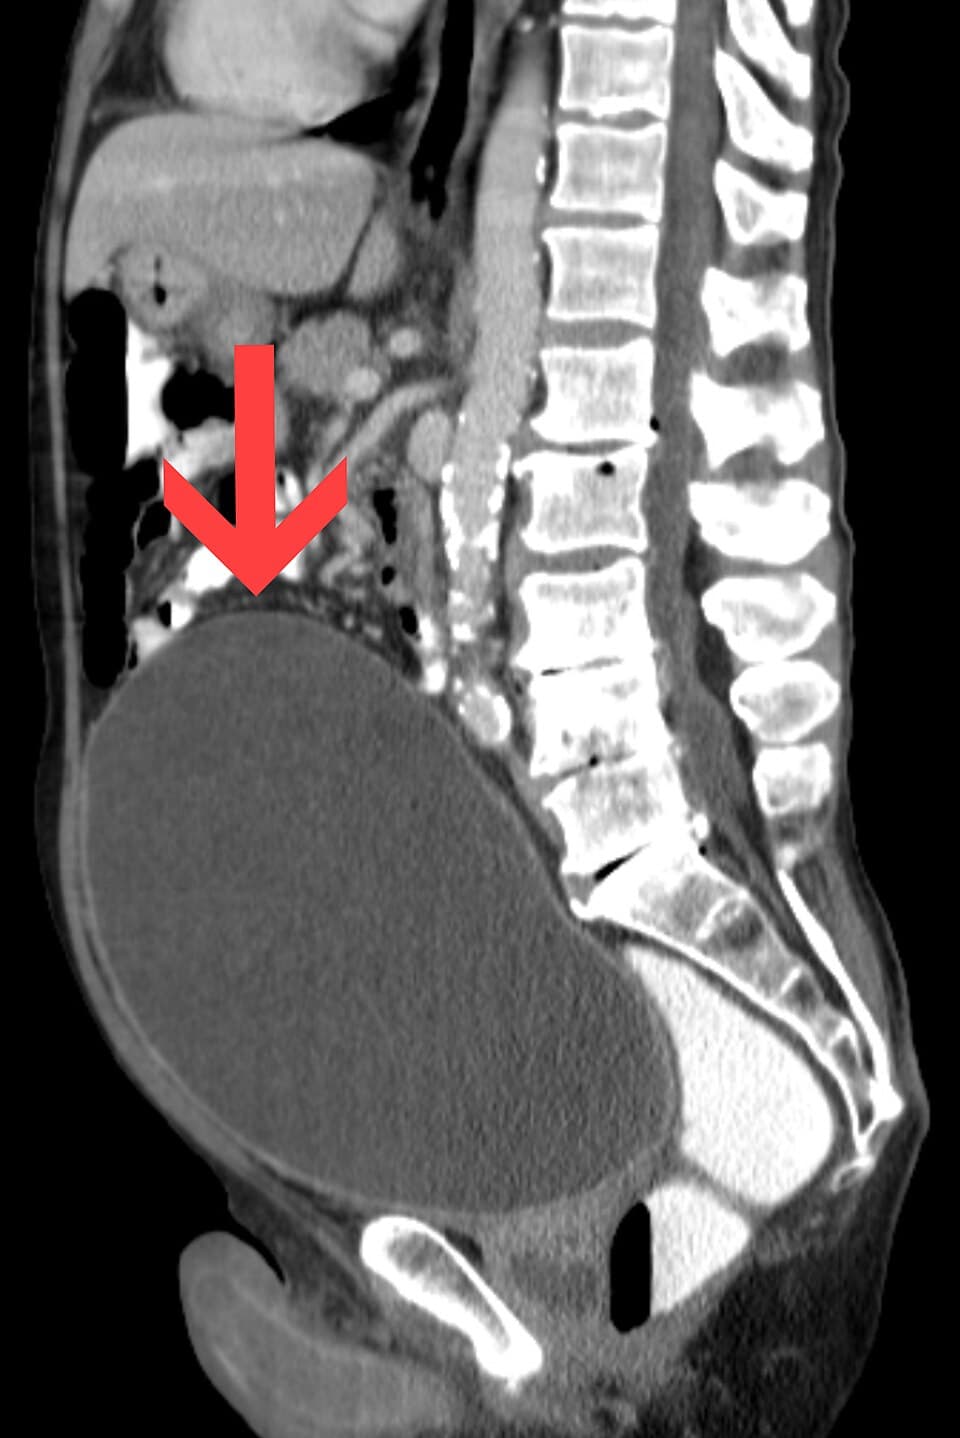

La est l'incapacité soudaine pour un individu d'émettre des urines alors qu'il a la vessie pleine. Le volume de la vessie augmente alors. On parle parfois ainsi de globe vésical. La capacité de la vessie est importante, mais le volume déclenchant l'envie de miction est d'environ pour un adulte. Elle était appelée anciennement « ischurie ». Douleurs au niveau de l'hypogastre Absence d'émission d'urines depuis plusieurs heures Confusion, un état d'agitation. Il peut apparaître au-delà d'un certain volume d'urine, la rétention. L'examen physique montre une masse dans le bas ventre, au-dessus du pubis, arrondie, tendue, et mate à la percussion. Anurie : absence de production d'urine lors d'un état de choc. Fécalome : peut être associé, peut entraîner une rétention aiguë d'urines et peut être une autre cause de confusion. Rétention urinaire chronique : pesanteur pelvienne ; pollakiurie ; dysurie ; jet de mauvaise qualité ; sensation de mauvaise vidange vésicale. La plus fréquente des complications est l'infection urinaire : cystite d'abord, pyélonéphrite ensuite. Lorsqu'elle est chronique, la rétention provoque une distension de la vessie avec atonie du détrusor, hypertrophie du détrusor ou diverticules vésicaux. La rétention urinaire pourrait provoquer un refoulement de l'urine vers les reins, causant une hydronéphrose. Hypertrophie bénigne de la prostate (adénome de prostate) Cancer de la prostate Calcul ou caillot sanguin dans l'urètre Tumeur Hypoactivité vésicale Phimosis Valve de l'urètre postérieur Sténose urétrale traumatique Compression urétrale extrinsèque : fécalome, tumeur pelvienne Anticholinergiques (parasympathycolytiques) (antispasmodiques, antidépresseurs tricycliques, certains antalgiques) Antiparkinsoniens Antihistaminiques Antihypertenseurs Opiacés et opioïdes Trouble sphinctérien d'origine neurologique : paraplégie ; syndrome de la queue de cheval ; sclérose en plaques. Le but est d'évacuer l'urine. Un sondage vésical, anciennement appelé sondage urinaire, ou une ponction sus-pubienne est nécessaire en cas de persistance.